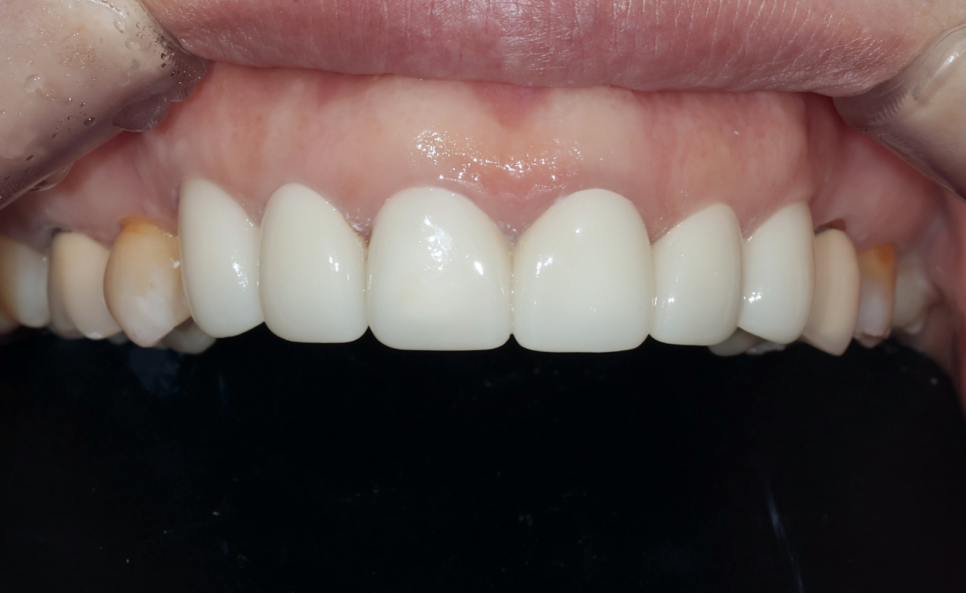

최종 결과 – 자연스럽고 조화로운 앞니 완성

최종 보철 완성 – 모든 치아가 자연스럽게 정리된 모습. 가운데 두 앞니는 연결 크라운으로 제작했습니다

약 3개월간의 임시 크라운 기간을 거친 후, 환자분이 다시 한국에 방문하셨을 때 최종 PFZ 크라운 6개를 세팅했습니다.

치료 전후를 비교하면 다음과 같은 개선이 이루어졌습니다.

| 치아 사이 검은 삼각형 공간(블랙트라이앵글) | 블랙트라이앵글 대폭 개선 |

| 앞니 사이 벌어진 공간 | 공간 해소, 가지런한 배열 |

| 크라운 변색, 색상 부조화 | 자연스럽고 균일한 색조 |

| 크라운 마진 부적합 | 정밀한 마진 적합 |

| 앞니 사이 다시 벌어질 위험 | 연결 크라운으로 재벌어짐 방지 |

| 입술 돌출 우려 | 평탄한 크라운 윤곽으로 입술 라인 개선 |

아랫니와도 자연스러운 조화를 이루는 모습